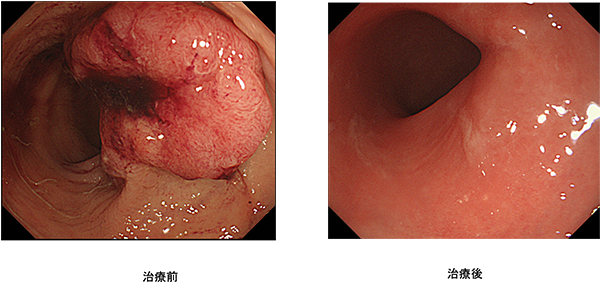

政府の「がん医療の均てん化政策(https://www.mhlw.go.jp/stf/shingi/other-kenkou_128568.html)により、多くの病院で良質ながん医療を受けることができるようになってきました。近年では、地域の拠点となる病院では、より高度で専門的ながん医療を行うことを目指した「がん医療の集約化」が重要視されています。そうした中、私達は本邦のガイドライン(https://www.jsccr.jp/guideline/index.html)だけではなく、欧米のガイドライン(https://www.nccn.org/guidelines/category_1)、(http://interactiveguidelines.esmo.org/esmo-web-app/toc/index.php?subjectAreaId=3&loadPdf=1)や大規模な臨床試験など、常に最新のがん治療にアンテナを張り、その時点で最良と思われる治療を提供できるように努めています。また、他の病院では手術ができないと言われたような場合や人工肛門が必要だと言われた場合でも、本当にできないのか、人工肛門を回避できる方法はないのかなど、内科や放射線科、病理診断科など、がんを専門とする複数の診療科とともに合同カンファレンスを行い、最適な治療法を常に模索しています(図1-5)。

ロボット支援下手術により安全に吻合できるようになったため人工肛門が回避できた。